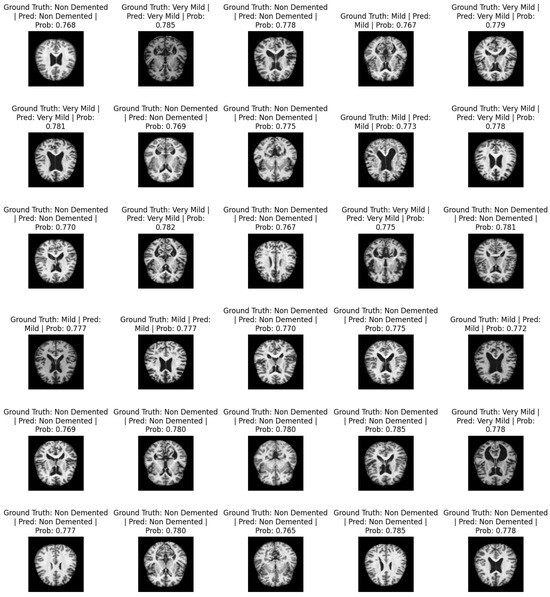

Figure 4 shows a sample of predicted images. It contains information about the actual labels and predicted labels: i.e., ground truth and prediction. For each image, the classification probabilities ranging from 0 and 1 show the probability of the image being classified as one of the respective classes. The total number of classes is non-demented, mild, moderate demented, and very mild.

Figure 4. Predicted AD classification.

Mathematics 13 01927 g004